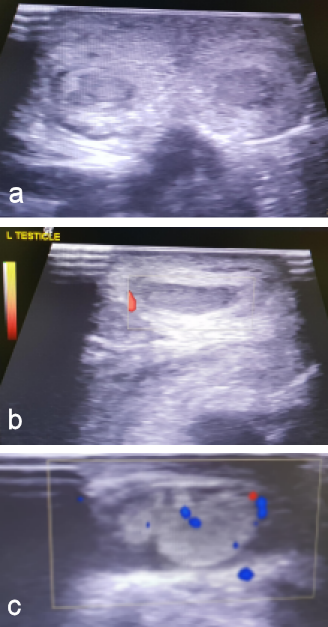

The child was managed non-operatively. He was monitored clinically and radiologically. In the following days, the testicles maintained their normal echogenic structure and vascularity, however, thickening of the scrotum wall was still observed in the context of hematoma, while at the same time a hydrocele with echogenic elements on the left scrotum (hematoma) was observed to be more intensive (Figure 3a, b, c [Fig. 3]). Follow-up ultrasound scans revealed complete resolution of the earlier noted hematoma at the scrotal wall.

Figure 3: a) Ultrasonography of both testicles. b) Doppler ultrasonography of the right testicle. c) Doppler ultrasonography of the left testicle. Both testicles maintain their normal echogenic structure and vascularity. Thickening of the scrotum wall is still observed in the context of hematoma. A hydrocele with echogenic elements on the left scrotum (hematoma) is observed.